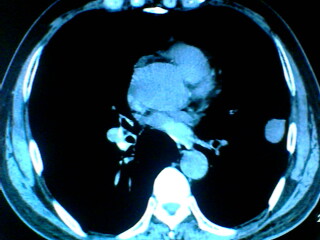

老年男性患者,右侧胸疼1月余(不是左侧),无其他症状

左肺外周类圆形病灶,其内低密度,可见液平及气影,周围肺文理见渗出样变,考虑左肺外周带肺脓肿。

左肺舌叶胸膜下卵圆形囊性肿块,内有液-气平面,邻近胸膜无增厚,没有肺窗,周围情况显示不清,考虑胸膜下肺囊肿并感染,病人年龄较大,有胸痛应警惕其他,但神经源性肿瘤暂不考虑。